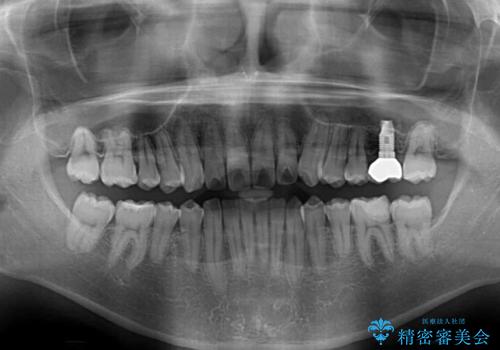

奥歯の虫歯は抜歯が必要であったので、矯正治療前に抜歯をし、矯正治療と並行してインプラントによる補綴治療を行うこととしました。

当院の特徴は、矯正治療とインプラント補綴治療の担当医が同じ歯科医師であるため、両方の治療を並行して行うことができます。